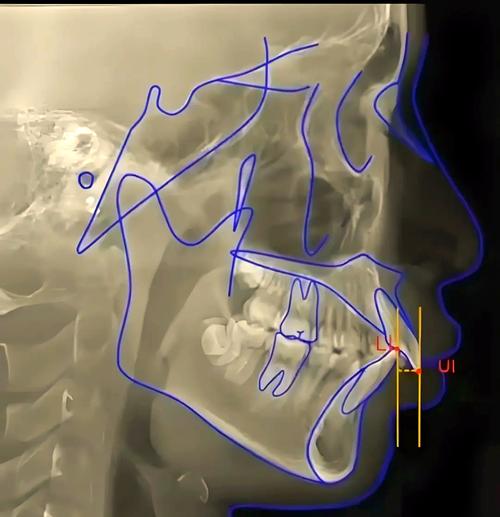

正畸头影测量图的核心价值在于“量化分析”,其通过标志点(如Sella点、Nasion点、A点、B点等)和参考平面(如FH平面、SN平面、PP平面、MP平面等),测量骨骼角度(如ANB角、SN-MP角)、牙齿位置(如U1-NA距、L1-NB距)、软组织形态(如鼻唇角、颏唇沟深度)等关键指标,为医生提供客观依据,在骨性Ⅲ类错颌的诊断中,ANB角<0°且SNB角增大提示下颌发育过度;在拥挤度分析中,通过牙冠宽度与牙弓可用空间的差值,可精准判断是否需要拔牙。

(图片来源网络,侵删) -